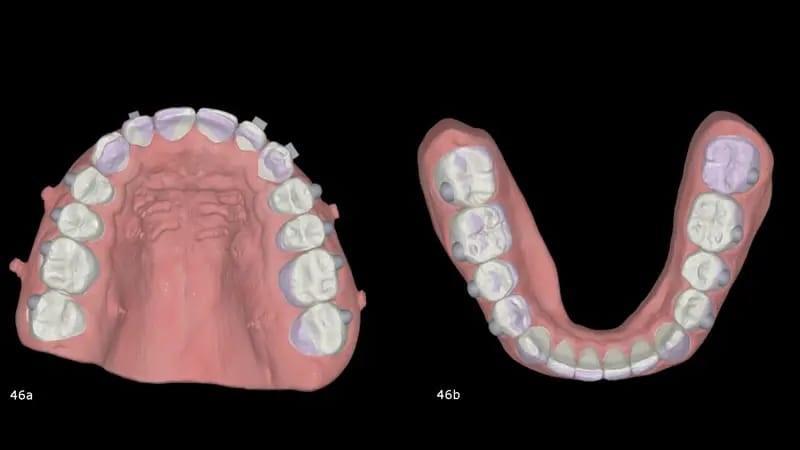

Как только прикус закрылся, лечение продолжили с помощью элайнеров в обеих дугах. Цели на этом этапе состояли в том, чтобы приложить положительный крутящий момент к резцам верхней челюсти и клыкам и слегка втянуть резцы нижней челюсти, а также использовать IPR для улучшения горизонтального перекрытия верхних и нижних передних зубов и достижения идеальной задней интеркуспации (фото 46). Всего было запланировано десять элайнеров для верхней и нижнечелюстной области, после чего был проведен дополнительный этап доработки с использованием еще десяти элайнеров для каждой дуги для окончательной обработки и детализации. Общее время лечения, включая первоначальную шинотерапию, составило 17 месяцев.

Фото 46a-b: 3D наложение запланированных движений с помощью элайнеров.